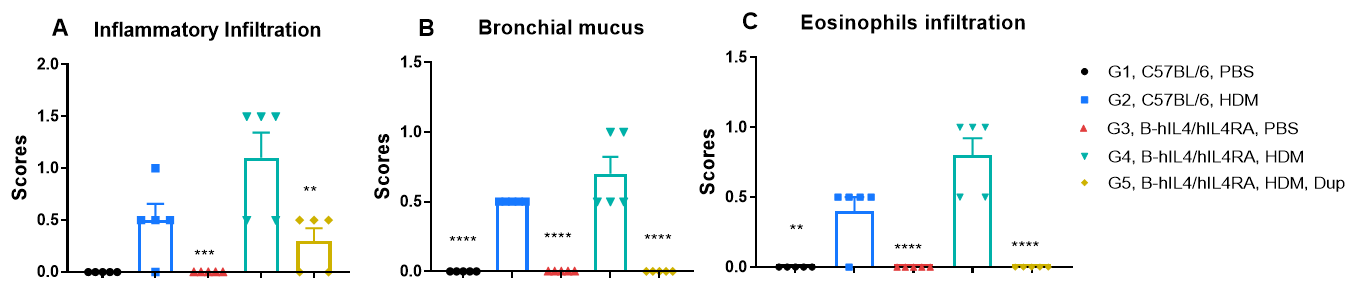

Efficacy of anti-human TSLP antibody (Tezepelumab) in hTSLP/OVA-induced asthma model of TSLP and TSLP receptor humanized (B-hTSLP/hTSLPR) mice. OVA/TSLP sensitization induced asthma in B-hTSLP/hTSLPR mice, as evidenced by significantly elevated CD45⁺ leukocyte counts, eosinophil numbers, and eosinophil proportions in bronchoalveolar lavage fluid (BALF) in G2 compared to G1 controls. Tezepelumab (in-house) treatment markedly reduced CD45⁺ cells and eosinophils. At endpoint, BALF TARC levels and serum total IgE concentrations, measured by ELISA, were also significantly increased in G2 and reduced following tezepelumab administration, confirming the therapeutic efficacy of TSLP blockade in this allergic asthma model.